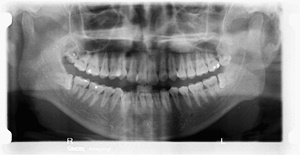

사랑니란?

우리가 사랑니라고 부르는 것은 큰 어금니 중 세 번째 위치에서 제일 마지막에 나오는 치아입니다. 사랑니가 나올 때에는 첫사랑을 하듯이 아프다고 하여 붙여진 이름이라고 하는데요. 다른 이름으로는 ‘지치’라고 합니다. 지치는 사리를 분별할 수 있는 지혜가 생긴다는 뜻입니다.

사랑니는 보통 큰 어금니와 비슷하게 생겼습니다. 사랑니의 형태나 크기는 매우 다양하다고 하는데요. 보통의 어금니 보다 깊이 나기 때문에 빼기 어렵거나 절개를 통해 힘들게 빼야 하는 경우가 많습니다. 원래 사랑니는 음식물을 갈아 내기 위한 용도라고 하는데요. 이것은 치아의 퇴화 현상이라고 생각하시는 분들도 많이 계십니다.